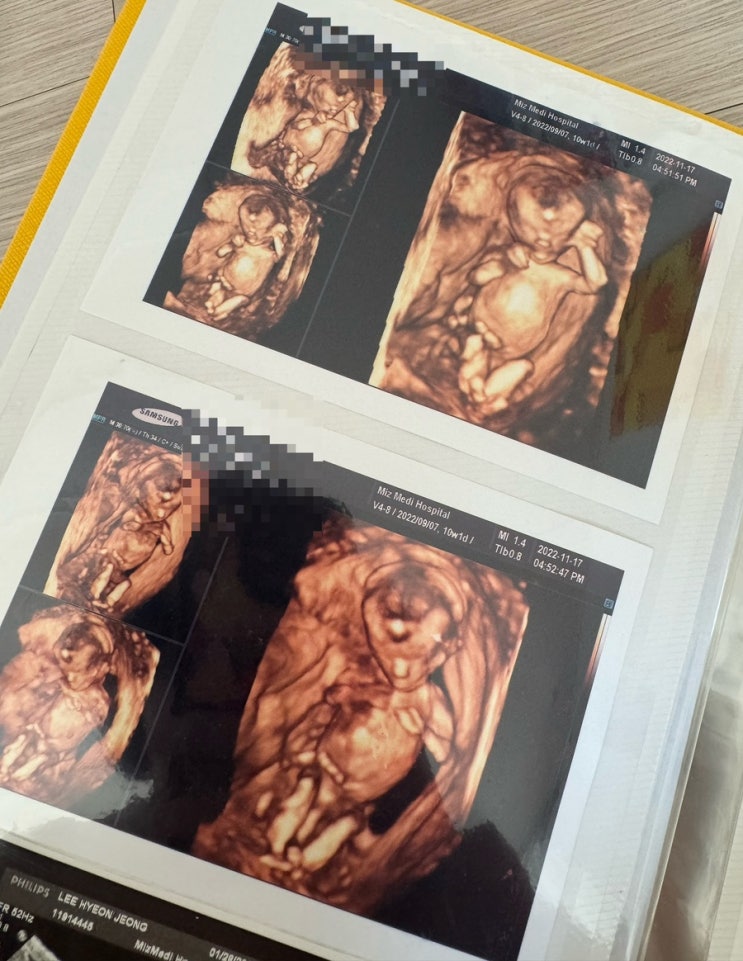

초음파 사진 정리

2년 전쯤에는 태아였는데 이렇게 이렇게 커서 말을 안듣고 지맘대로 하다니 ㅋㅋㅋㅋㅋㅋㅋㅋㅋㅋㅋㅋㅋㅋ ...